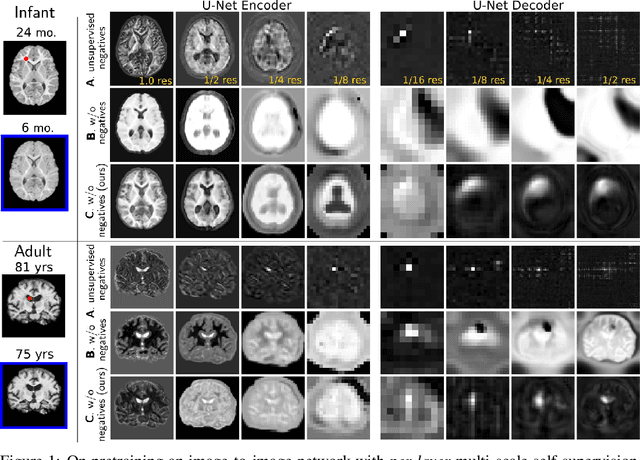

Abstract:Recent self-supervised advances in medical computer vision exploit global and local anatomical self-similarity for pretraining prior to downstream tasks such as segmentation. However, current methods assume i.i.d. image acquisition, which is invalid in clinical study designs where follow-up longitudinal scans track subject-specific temporal changes. Further, existing self-supervised methods for medically-relevant image-to-image architectures exploit only spatial or temporal self-similarity and only do so via a loss applied at a single image-scale, with naive multi-scale spatiotemporal extensions collapsing to degenerate solutions. To these ends, this paper makes two contributions: (1) It presents a local and multi-scale spatiotemporal representation learning method for image-to-image architectures trained on longitudinal images. It exploits the spatiotemporal self-similarity of learned multi-scale intra-subject features for pretraining and develops several feature-wise regularizations that avoid collapsed identity representations; (2) During finetuning, it proposes a surprisingly simple self-supervised segmentation consistency regularization to exploit intra-subject correlation. Benchmarked in the one-shot segmentation setting, the proposed framework outperforms both well-tuned randomly-initialized baselines and current self-supervised techniques designed for both i.i.d. and longitudinal datasets. These improvements are demonstrated across both longitudinal neurodegenerative adult MRI and developing infant brain MRI and yield both higher performance and longitudinal consistency.